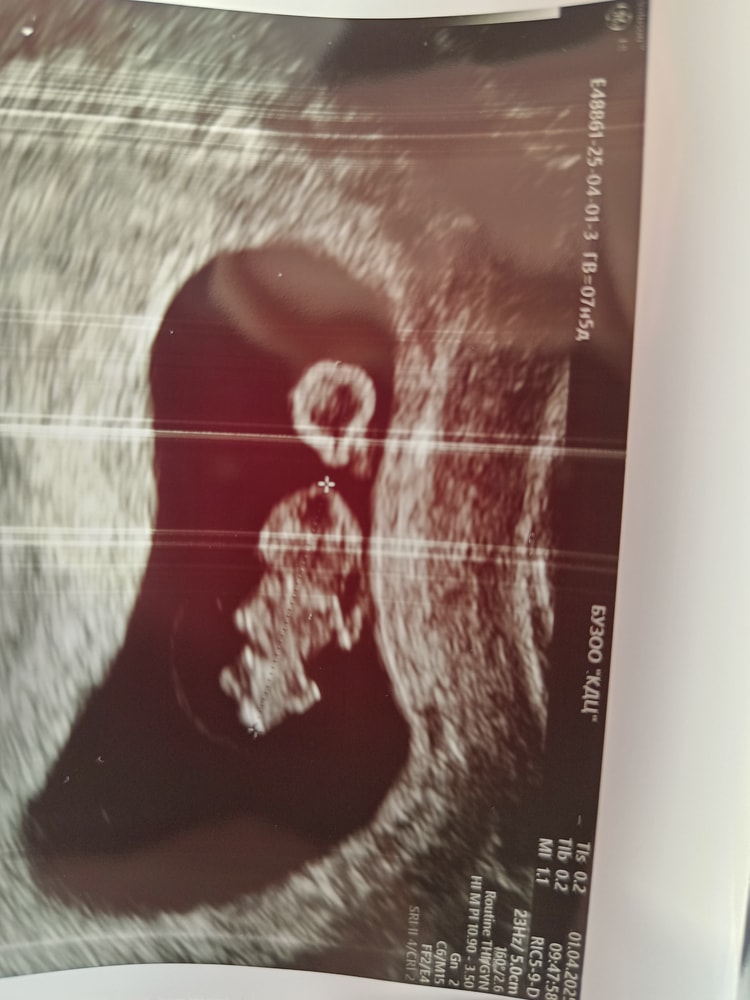

Узи 7+5

УЗИ, КТГ, доплерСходила на свидание с малышом 🥰

Как же он подрос уже! Еще неделю назад было как рисинка или фасоль, а тут уже человечек вырисовывается 😊

Ручки- ножки, понятно где что)

Ктр 14,1

Чсс 176

Желточный мешочек 2,5

Прикрепился ребеныш по задней стенке.